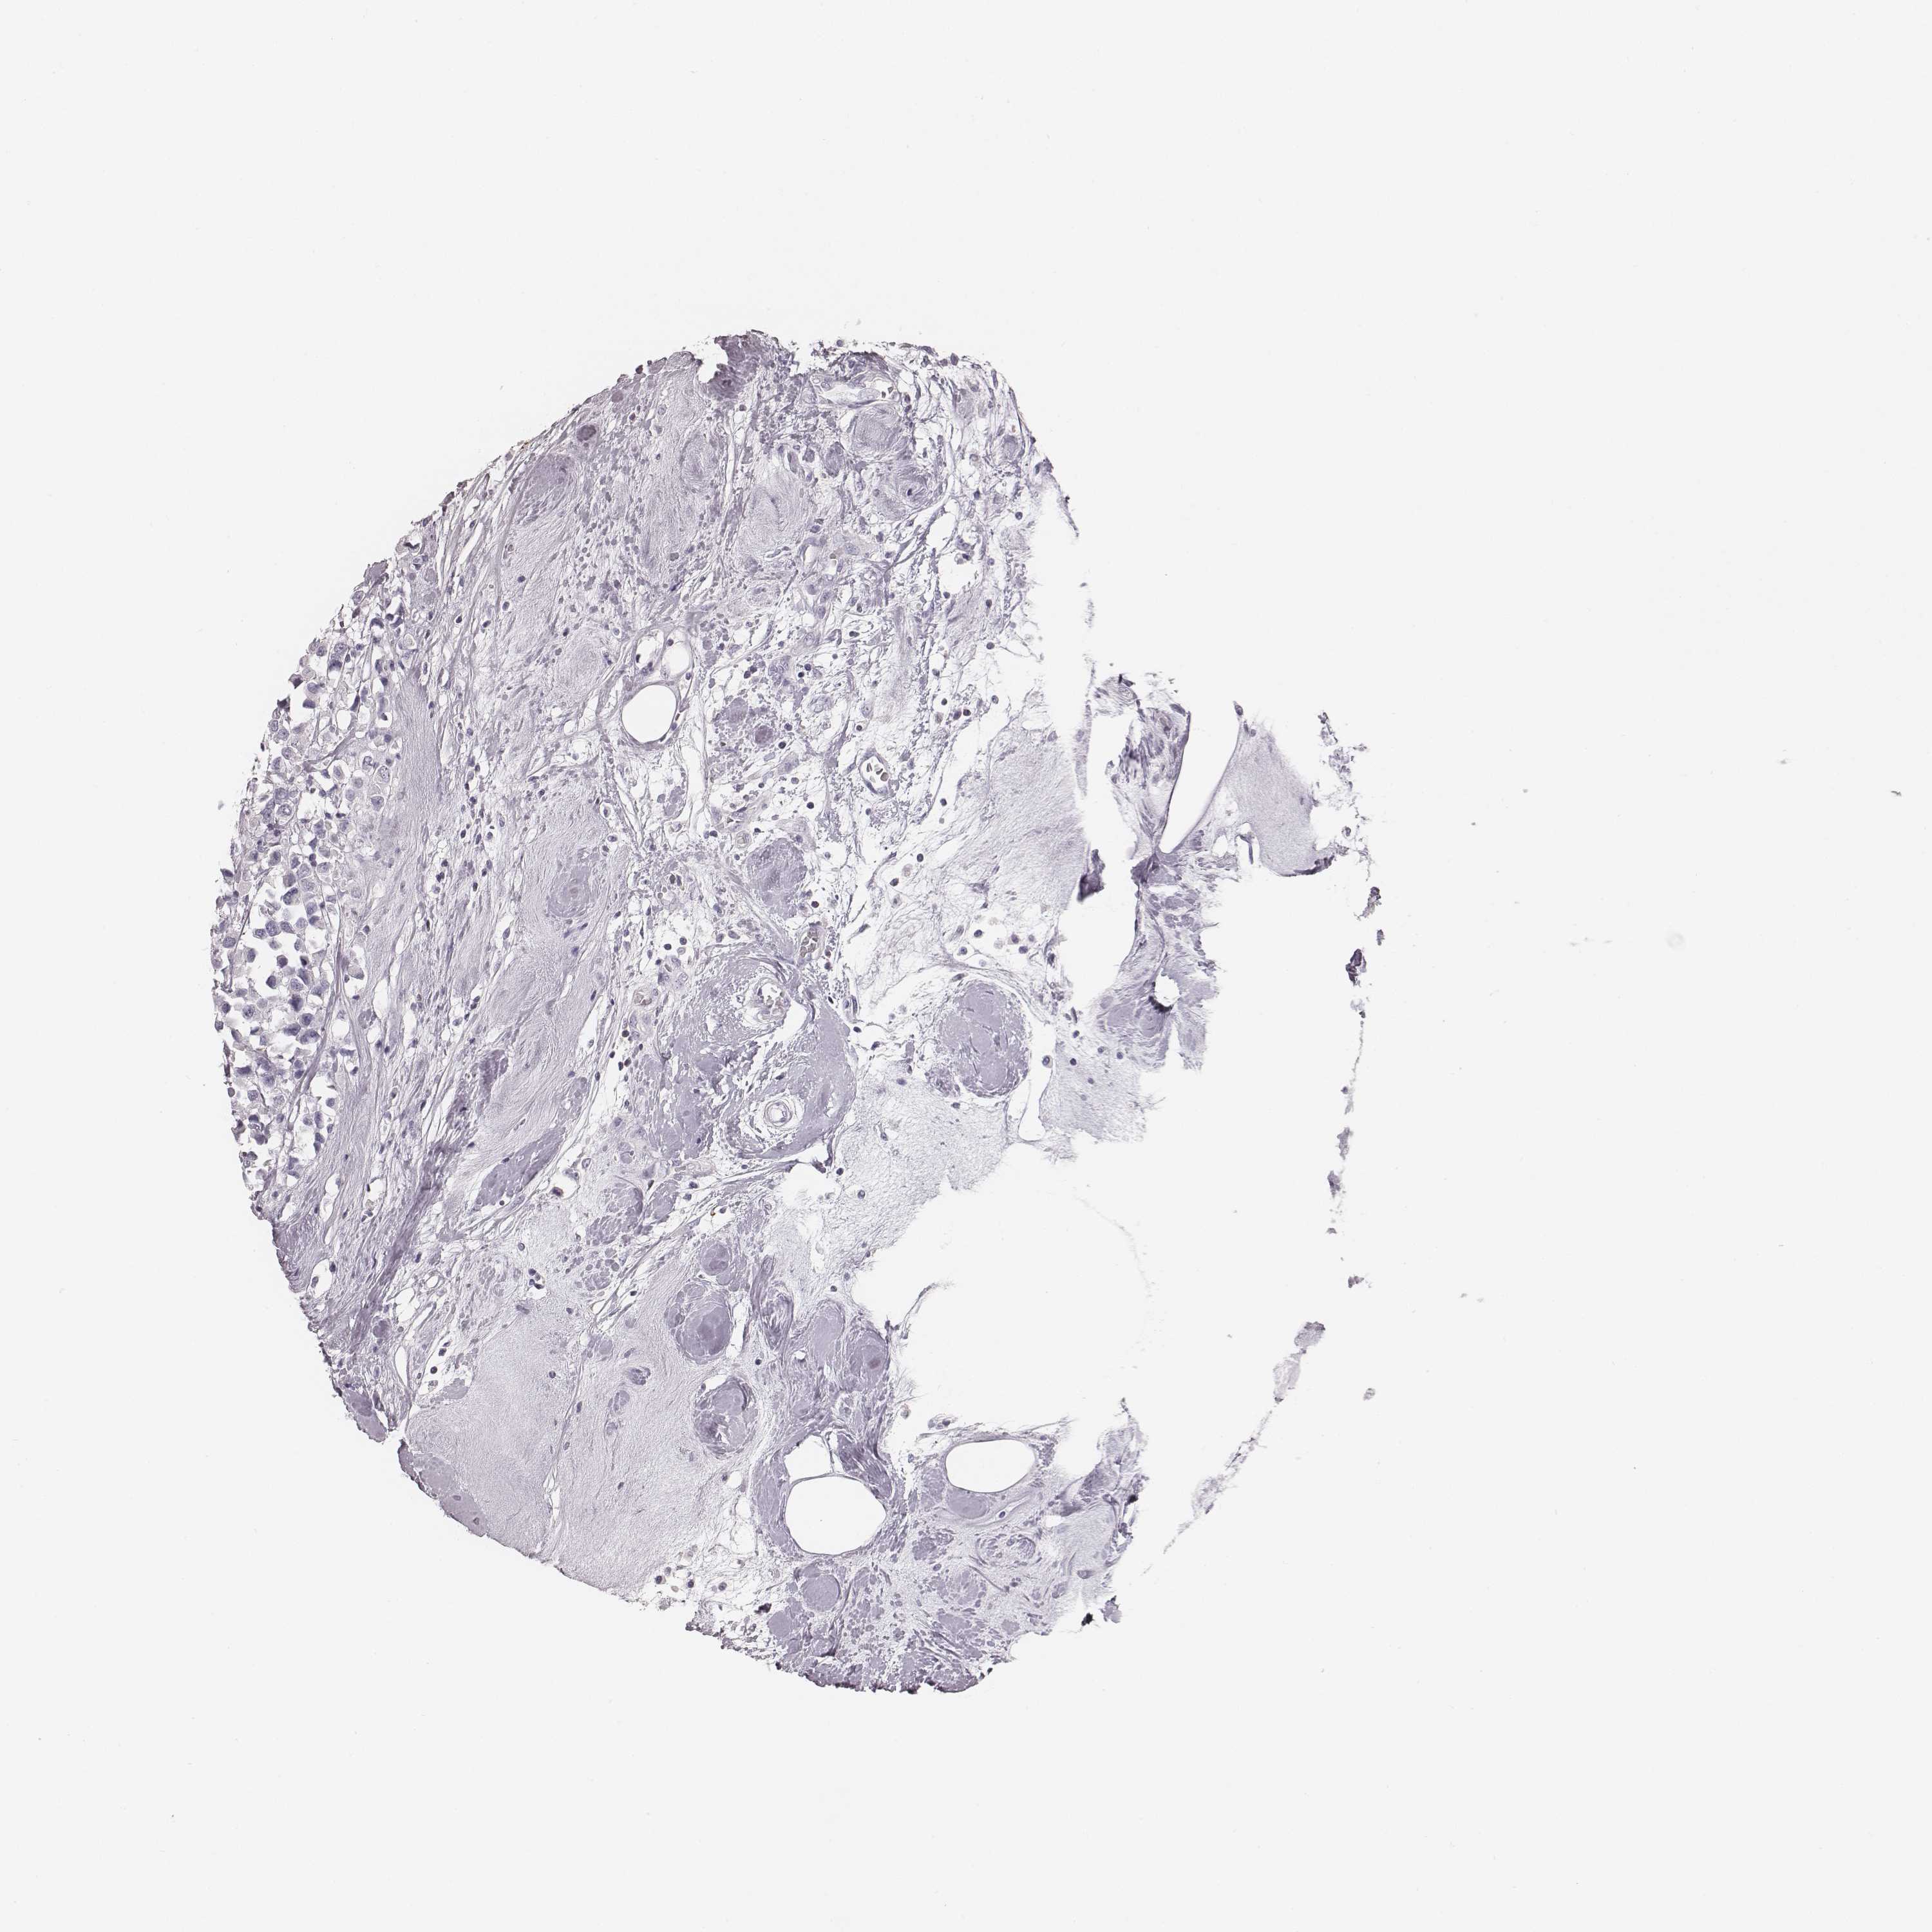

BRCA TCGA BRCA VALIDATION PROTEIN EXPRESSION

ANTIBODIES

AND

VALIDATION